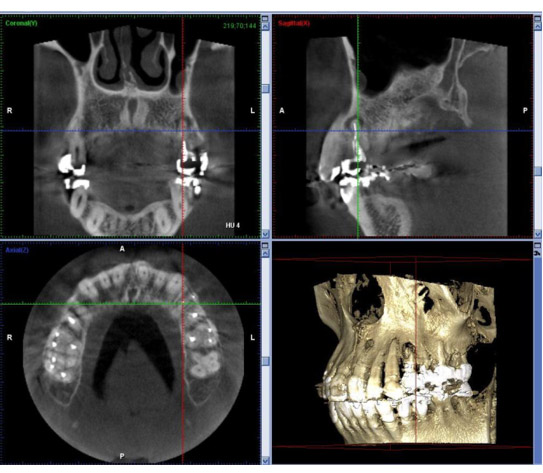

歯科用CTによる3Dレントゲン写真